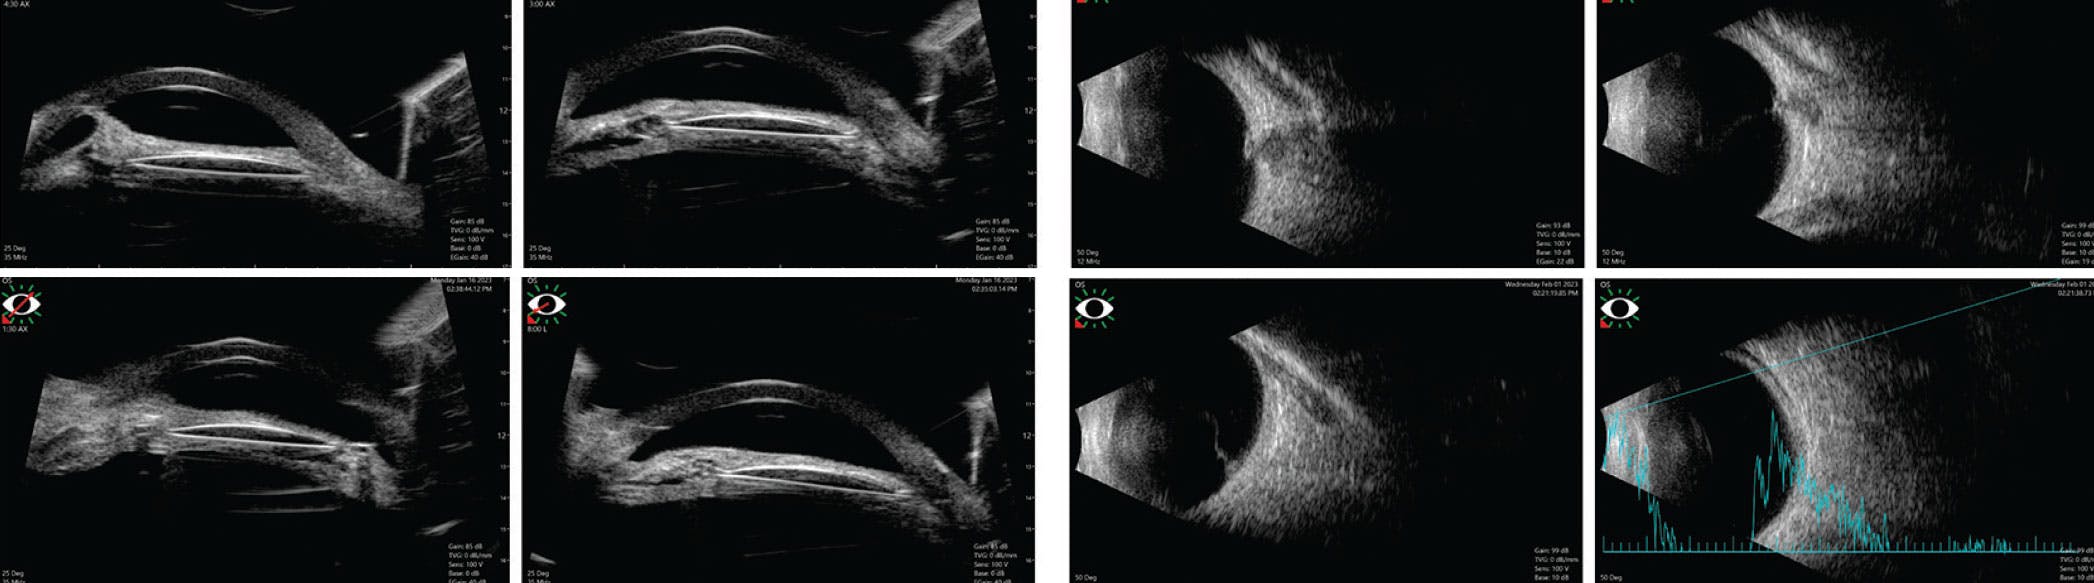

The third case describes a cyclitic membrane complicating open-globe injury. A 2.5-year-old girl with an open-globe injury and an open lens, who underwent primary repair with cataract extraction and IOL implantation, presented with a VA of light perception and the beginning stages of atrophia, with an axial length of 1 mm less in the right eye compared with the left. The patient was using steroid eye drops with slight hypotony. The eye also showed seclusio pupillae (Figure 5). Ultrasound biomicroscopy showed a membrane surrounding the IOL and dragging on the ciliary processes. Stretched iris and ciliary body were seen. B-scan showed a flat retina (Figure 6).

<p>Figure 6. Case 3 ultrasound biomicroscopy shows a cocoon surrounding the IOL and attached to the ciliary processes. B-scan shows the flat retina with minimal traction at the disc.</p>

Figure 6. Case 3 ultrasound biomicroscopy shows a cocoon surrounding the IOL and attached to the ciliary processes. B-scan shows the flat retina with minimal traction at the disc.